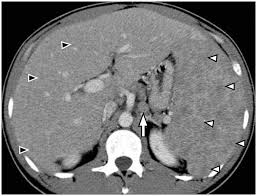

• Enlarged liver (hepatomegaly) on ultrasound or CT

• Imaging (ultrasound, CT, MRI)